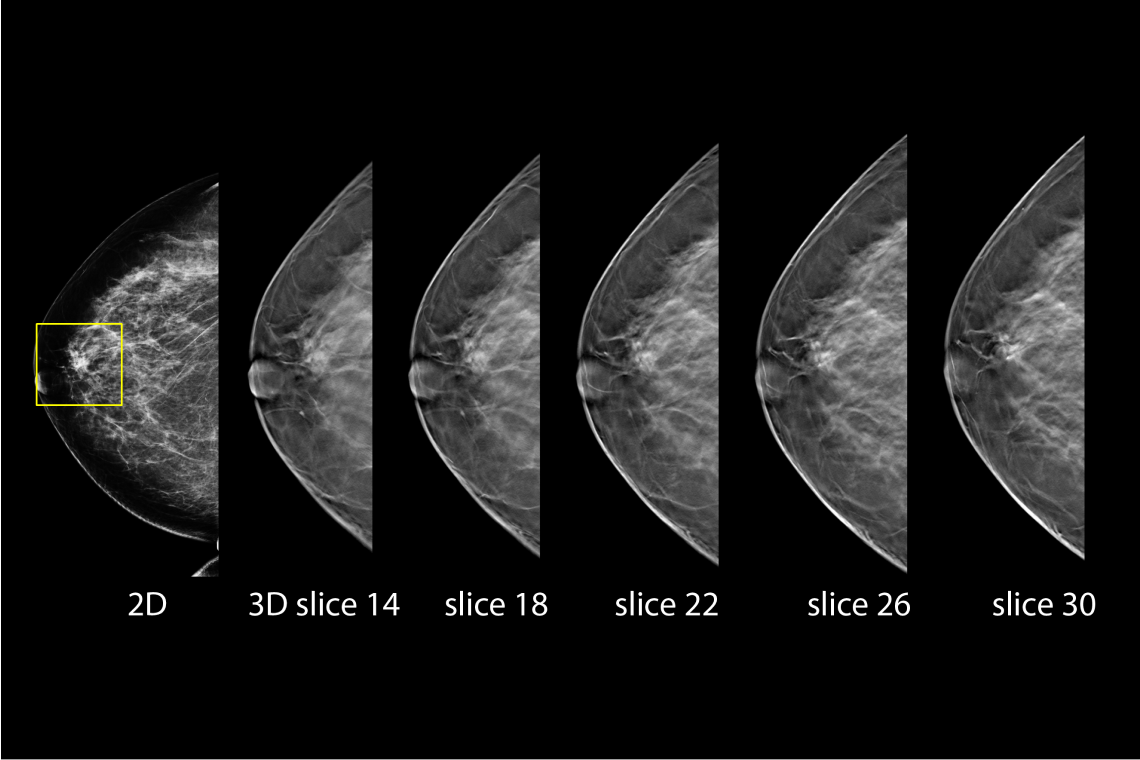

Gelişmiş 3D Tomosentez Teknolojisi

Hologic Selenia® Dimensions, FDA onaylı Genius™ 3D tomosentez teknolojisi ile meme dokusunu yüksek çözünürlükte katman katman tarar. Bu ileri teknoloji, geleneksel 2D mamografiye kıyasla meme kanserini %20 ile %65 arasında daha yüksek oranda tespit ederek erken teşhiste önemli bir avantaj sunar. Klinik çalışmalar, bu sistemin yalancı pozitif çağrı oranlarını %40’a kadar azaltarak gereksiz biyopsi sayısının düşürülmesini sağladığını ortaya koymaktadır. Özellikle yoğun ve karmaşık meme yapısına sahip hastalarda, lezyonların daha net görünmesini mümkün kılarak radyologların tanı güvenilirliğini artırır.

Clarity HD Yüksek Çözünürlüklü Görüntüleme ile Tanıda Netlik

Clarity HD™ teknolojisi, Hologic’in dijital mamografi sistemlerinde yer alan yüksek çözünürlüklü 3D görüntüleme teknolojisidir. Bu sistem, meme dokusunu 70 mikron çözünürlükle katman katman tarayarak olağanüstü netlikte tomosentez görüntüleri sunar. Sonuç: daha doğru tanılar, daha az tekrar çekim ve daha güvenli tarama kararları.

Özellikle yoğun meme dokusuna sahip hastalarda, Clarity HD, dokuların üst üste binmesini önleyerek küçük kitleler, gizli kalsifikasyonlar ve diğer anormalliklerin (örneğin spiküler lezyonlar veya distorsiyonlar) daha görünür hale gelmesini sağlar. Bu da erken evre meme kanserinin tespiti açısından kritik öneme sahiptir. Geleneksel 2D sistemlerle karşılaştırıldığında, Clarity HD ile elde edilen görüntü netliği %50’ye kadar artarken, belirsiz tanılar nedeniyle istenen ileri görüntüleme oranları %40’a kadar azalmaktadır.